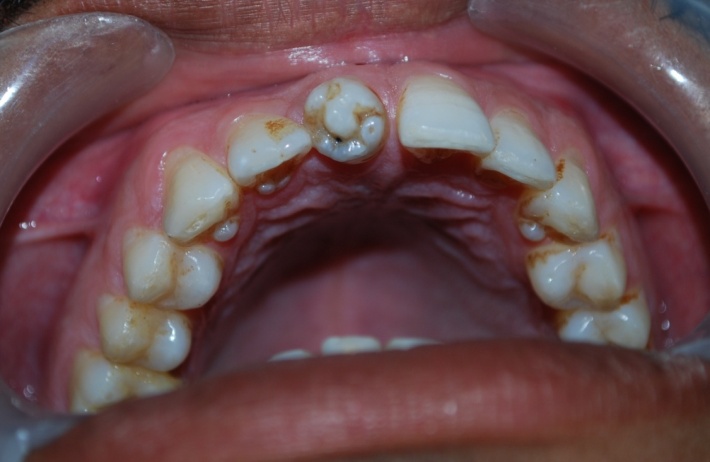

A 32-year-old male patient reported to the Department of Oral Medicine and Radiology for routine check-up. This was the patient’s first visit to a dentist. His medical and family histories were non-contributory. There were no findings indicative of any syndrome. An intraoral examination of maxillary right central incisor revealed a morphologically altered crown with multiple small cusps and a prominent central cusp (Figures 1 and 2). There were 5 small cusps and a prominent central cusp. Presence of talon cusp in relation to teeth #12, #13 and #33 was also seen. Mild stains were present on the occlusal surface of central incisor with pit caries. Intraoral periapical radiograph revealed prominent talon cusp at the center surrounded by small cusps along with three impacted supernumerary teeth at the periapex. The root, lamina dura and periodontal ligament space of tooth #11 appeared to be normal (Figure 3). Examination of the remaining dentition showed no obvious abnormalities. The patient was told about the condition. Routine scaling and oral prophylaxis were performed. Prosthetic crown in relation to tooth #11 was planned to correct the esthetic appearance and surgical removal of impacted teeth was suggested. Since the patient was asymptomatic, he refused to undergo extraction of the impacted teeth. However, he was advised to undergo prophylactic enameloplasty of the talon cusps, followed by topical application of a desensitizing agent. He was also informed about the possible consequences of the impacted teeth and a regular clinical and radiographic follow-up of the impacted tooth was suggested.

Figure 3. Intraoral photograph showing an unusual and morphologically altered central incisor with 5 small cusps and large central cusp.